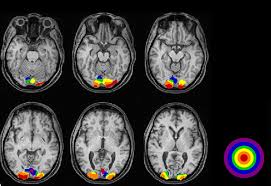

Somatosensory and visual processing in somatosensory and visual cortices of normal, blind and paraplegic subjects.

με θέμα: Ανταποκρίσεις οπτικών και σωματαισθητικών ερεθισμάτων σε οπτικές και σωματαισθητικές περιοχές του φλοιού σε υγιείς, τυφλούς και παραπληγικούς